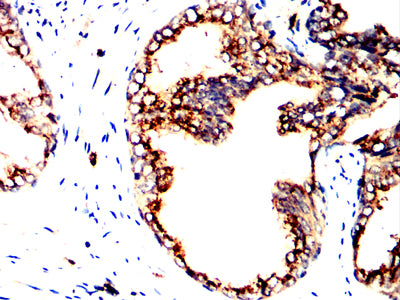

Immunohistochemical analysis of paraffin-embedded human prostate cancer tissues using PPID mouse mAb with DAB staining.